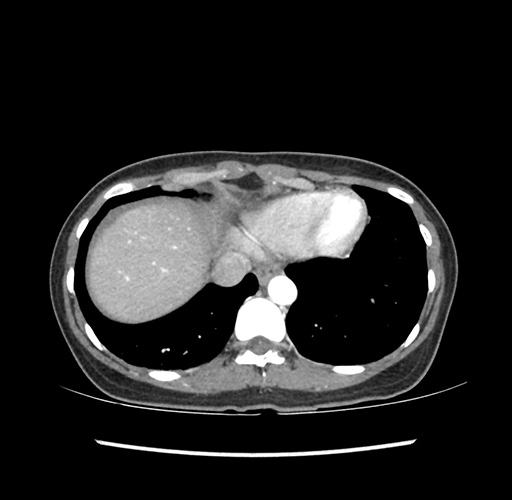

Imaging Analysis

Look through the patient's CT scan to identify any areas of concern for the necessary procedure.

Based on your CT findings, which issue(s) would give reason for "planned slowing down moment(s)" in this case?